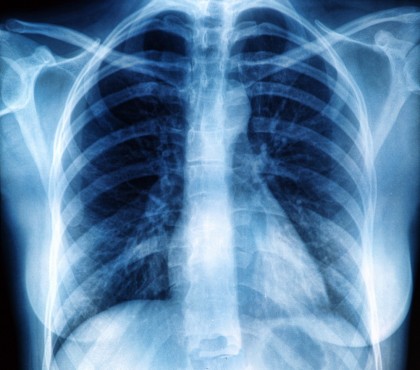

Lipsa detectării agentului patogen al tuberculozei Mycobacterium tuberculosis nu este o garanție pentru o vindecare permanentă a infecției pulmonare. Pacienții care răspund la terapia standard pot fi în afara tratamentului după șase luni. Dar pentru cazurile rezistente, se recomandă în prezent mai mult de 18 luni de tratament. Timpul este unul foarte lung și adesea determină apariția unor efecte adverse. Deoarece absența bacteriilor în spută nu justifică oprirea sigură a terapiei, o echipă de cercetători de la Centrul German de Cercetare a Infecțiilor, condusă de prof. Dr. Christoph Lange, director clinic la Centrul de Cercetare Borstel, și-a propus să găsească biomarkeri alternativi la pacient.

În colaborare cu centrele internaționale de TBC, pe baza cohortelor de pacienți ar putea fi dezvoltat un model pentru sfârșitul terapiei care se bazează pe o determinare a ARN-ului în sânge. Din multe mii de gene, au fost identificate 22 a căror activitate se corelează cu evoluția bolii. Pentru a identifica acest biomarker individual, oamenii de știință au stabilit cinci cohorte diferite de pacienți. În toate cazurile, subiecții au fost adulți care au contractat TB pulmonară, parțial din forme nerezistente, parțial din forme rezistente. Pe lângă cohortele din Germania, au fost incluși și pacienții din București (România).